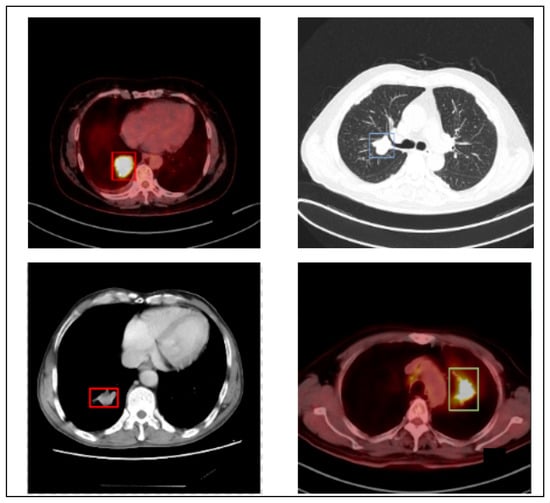

The author utilizes the PET/CT (Lung-PET-CT-Dx) dataset to generalize the proposed LC detection model. Lung-PET-CT-Dx is a recently developed dataset that comprises 31,562 annotated images. It is publicly available in the repository [36,37]. The images were retrospectively collected from multiple healthcare centers across China. The computer center and cancer institute, Harbin Medical University in Harbin, China, supported the dataset owners in obtaining permission to collect the PET/CT images. In addition, the patient’s personal information was not included in the dataset. The dataset contains CT and PET-CT DICOM images of LC patients. It provides XML annotation files to indicate tumor location and bounding boxes. The tissue histopathological diagnosis was used for the patients’ classification. The CT image resolution was 512 512 pixels at 1 mm 1 mm, and the PET image resolution was 200 200 pixels at 4.07 mm 4.07 mm. Five academic thoracic radiologists with expertise in LC detection were employed to annotate the tumor location. The Labellmg 1.4.0 package was used to capture the annotation. The images were broadly classified into adenocarcinoma (A), small cell carcinoma (B), large cell carcinoma (E), and squamous cell carcinoma (G). However, the dataset is highly imbalanced. Table 1 offers the dataset characteristics. Figure 2 highlights the sample LC images.

Figure 2.

Sample images.